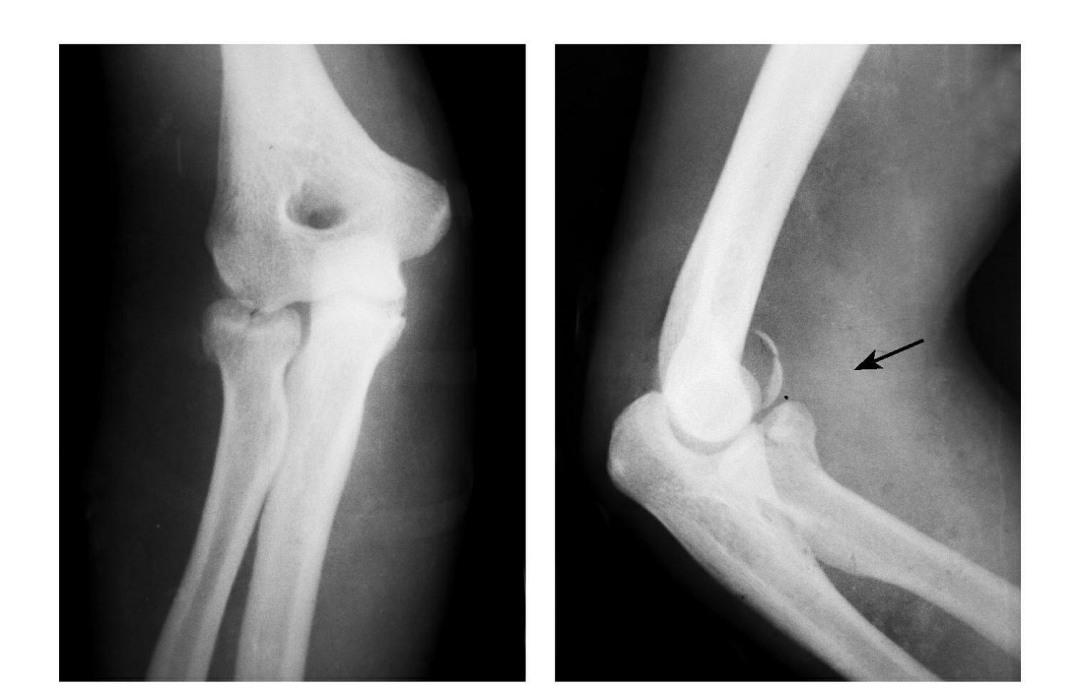

(2) Hill-Sachs、反 Hill-Sachs 损伤

肩关节脱位时,肱骨头和关节盂发生撞击,肱骨头表面凹陷性骨折。

肩关节前脱位时发生的肱骨头后外侧凹陷性骨折,是经典的 Hill-Sachs 损伤(Hill-Sachs lesion);而肩关节后脱位时发生的肱骨头前内侧凹陷性骨折,是反 Hill-Sachs 损伤(Reverse Hill-Sachs lesion/ McLaughlin lesion)。

1. 正位片示肱骨头损伤;2. 侧位片示反 Hill-Sachs 损伤;3.MRI 示反 Hill-Sachs 损伤程度。